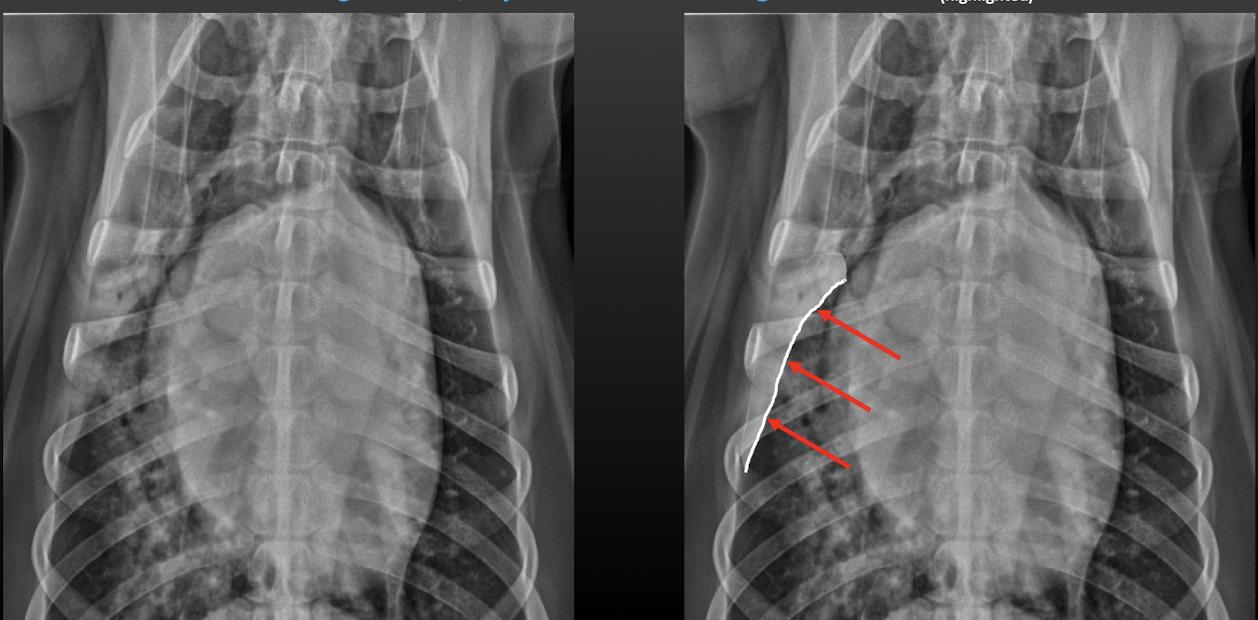

20

Q

Lung Pattern?

A

Alveolar

Lobar sign

21